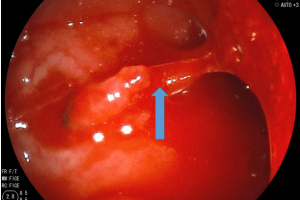

Vừa qua khoa cấp cứu bệnh viện Nhi đồng Thành phố, tiếp nhận một trường hợp trẻ Ng. H. T. D., 27 tháng tuổi, nam, cân nặng 12 kg, ngụ tại Tân Phú, TP HCM, được...